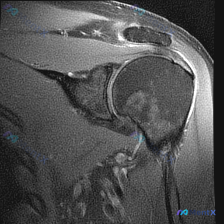

这是踝关节MRI矢状位T2序列图像,核心观察结果如下:

- 骨骼系统:胫骨远端、距骨、跟骨、舟骨骨皮质完整,未见明确骨折线;距骨体及跟骨骨髓信号均匀,无明显水肿或硬化改变

- 关节软骨:胫距关节对合良好,距骨滑车及胫骨远端关节软骨轮廓清晰,无明显局灶缺损或剥脱

- 韧带肌腱:跟腱走行连续,形态信号正常;屈趾长肌腱、屈拇长肌腱走行连续,未见异常

- 软组织与病变:踝关节前、后隐窝,距下关节间隙可见明确T2高信号,边界清晰,符合关节积液表现;皮下脂肪层信号均匀,无关节外弥漫性软组织水肿;后踝周围未见异常肿块或明显水肿